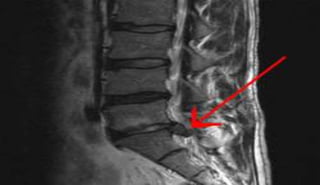

MRI lumber spine;

Intervertebral disc protrusion.

Compression of nerve root.